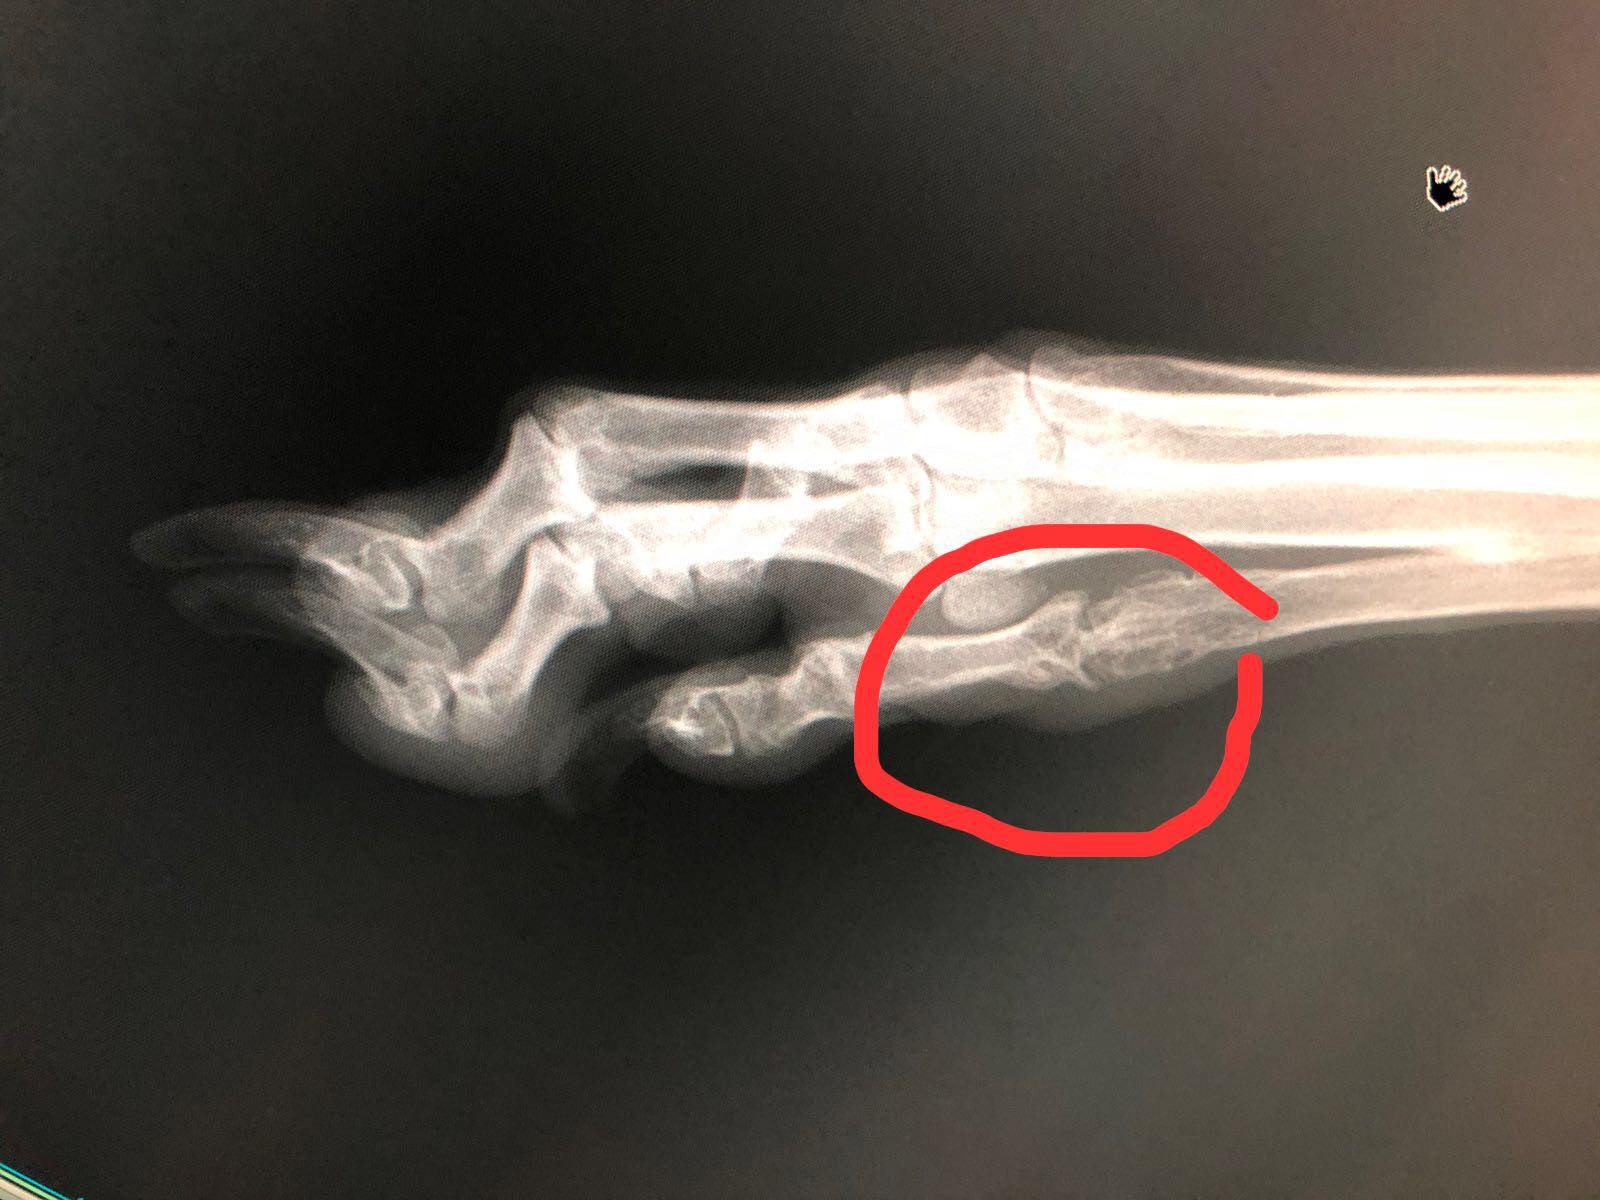

澳門愛護動物協會主席Albano Martins在星期二(7月10日)於社交媒體Facebook表示,成功拯救了一隻有腳傷的雄性格力犬Ko Ko,約6歲半。Albano Martins表示,Ko Ko本是被一名內地人領養的,後來將牠遺棄於澳門政府狗房,澳門愛協同日便到狗房接走Ko Ko。愛協其後帶Ko Ko到獸醫診所作檢查,Albano Martins上傳了幾張Ko Ko腳部的X光照片,指牠腳部受傷。

Ko Ko腳部的X光照片 (Albano Martins)